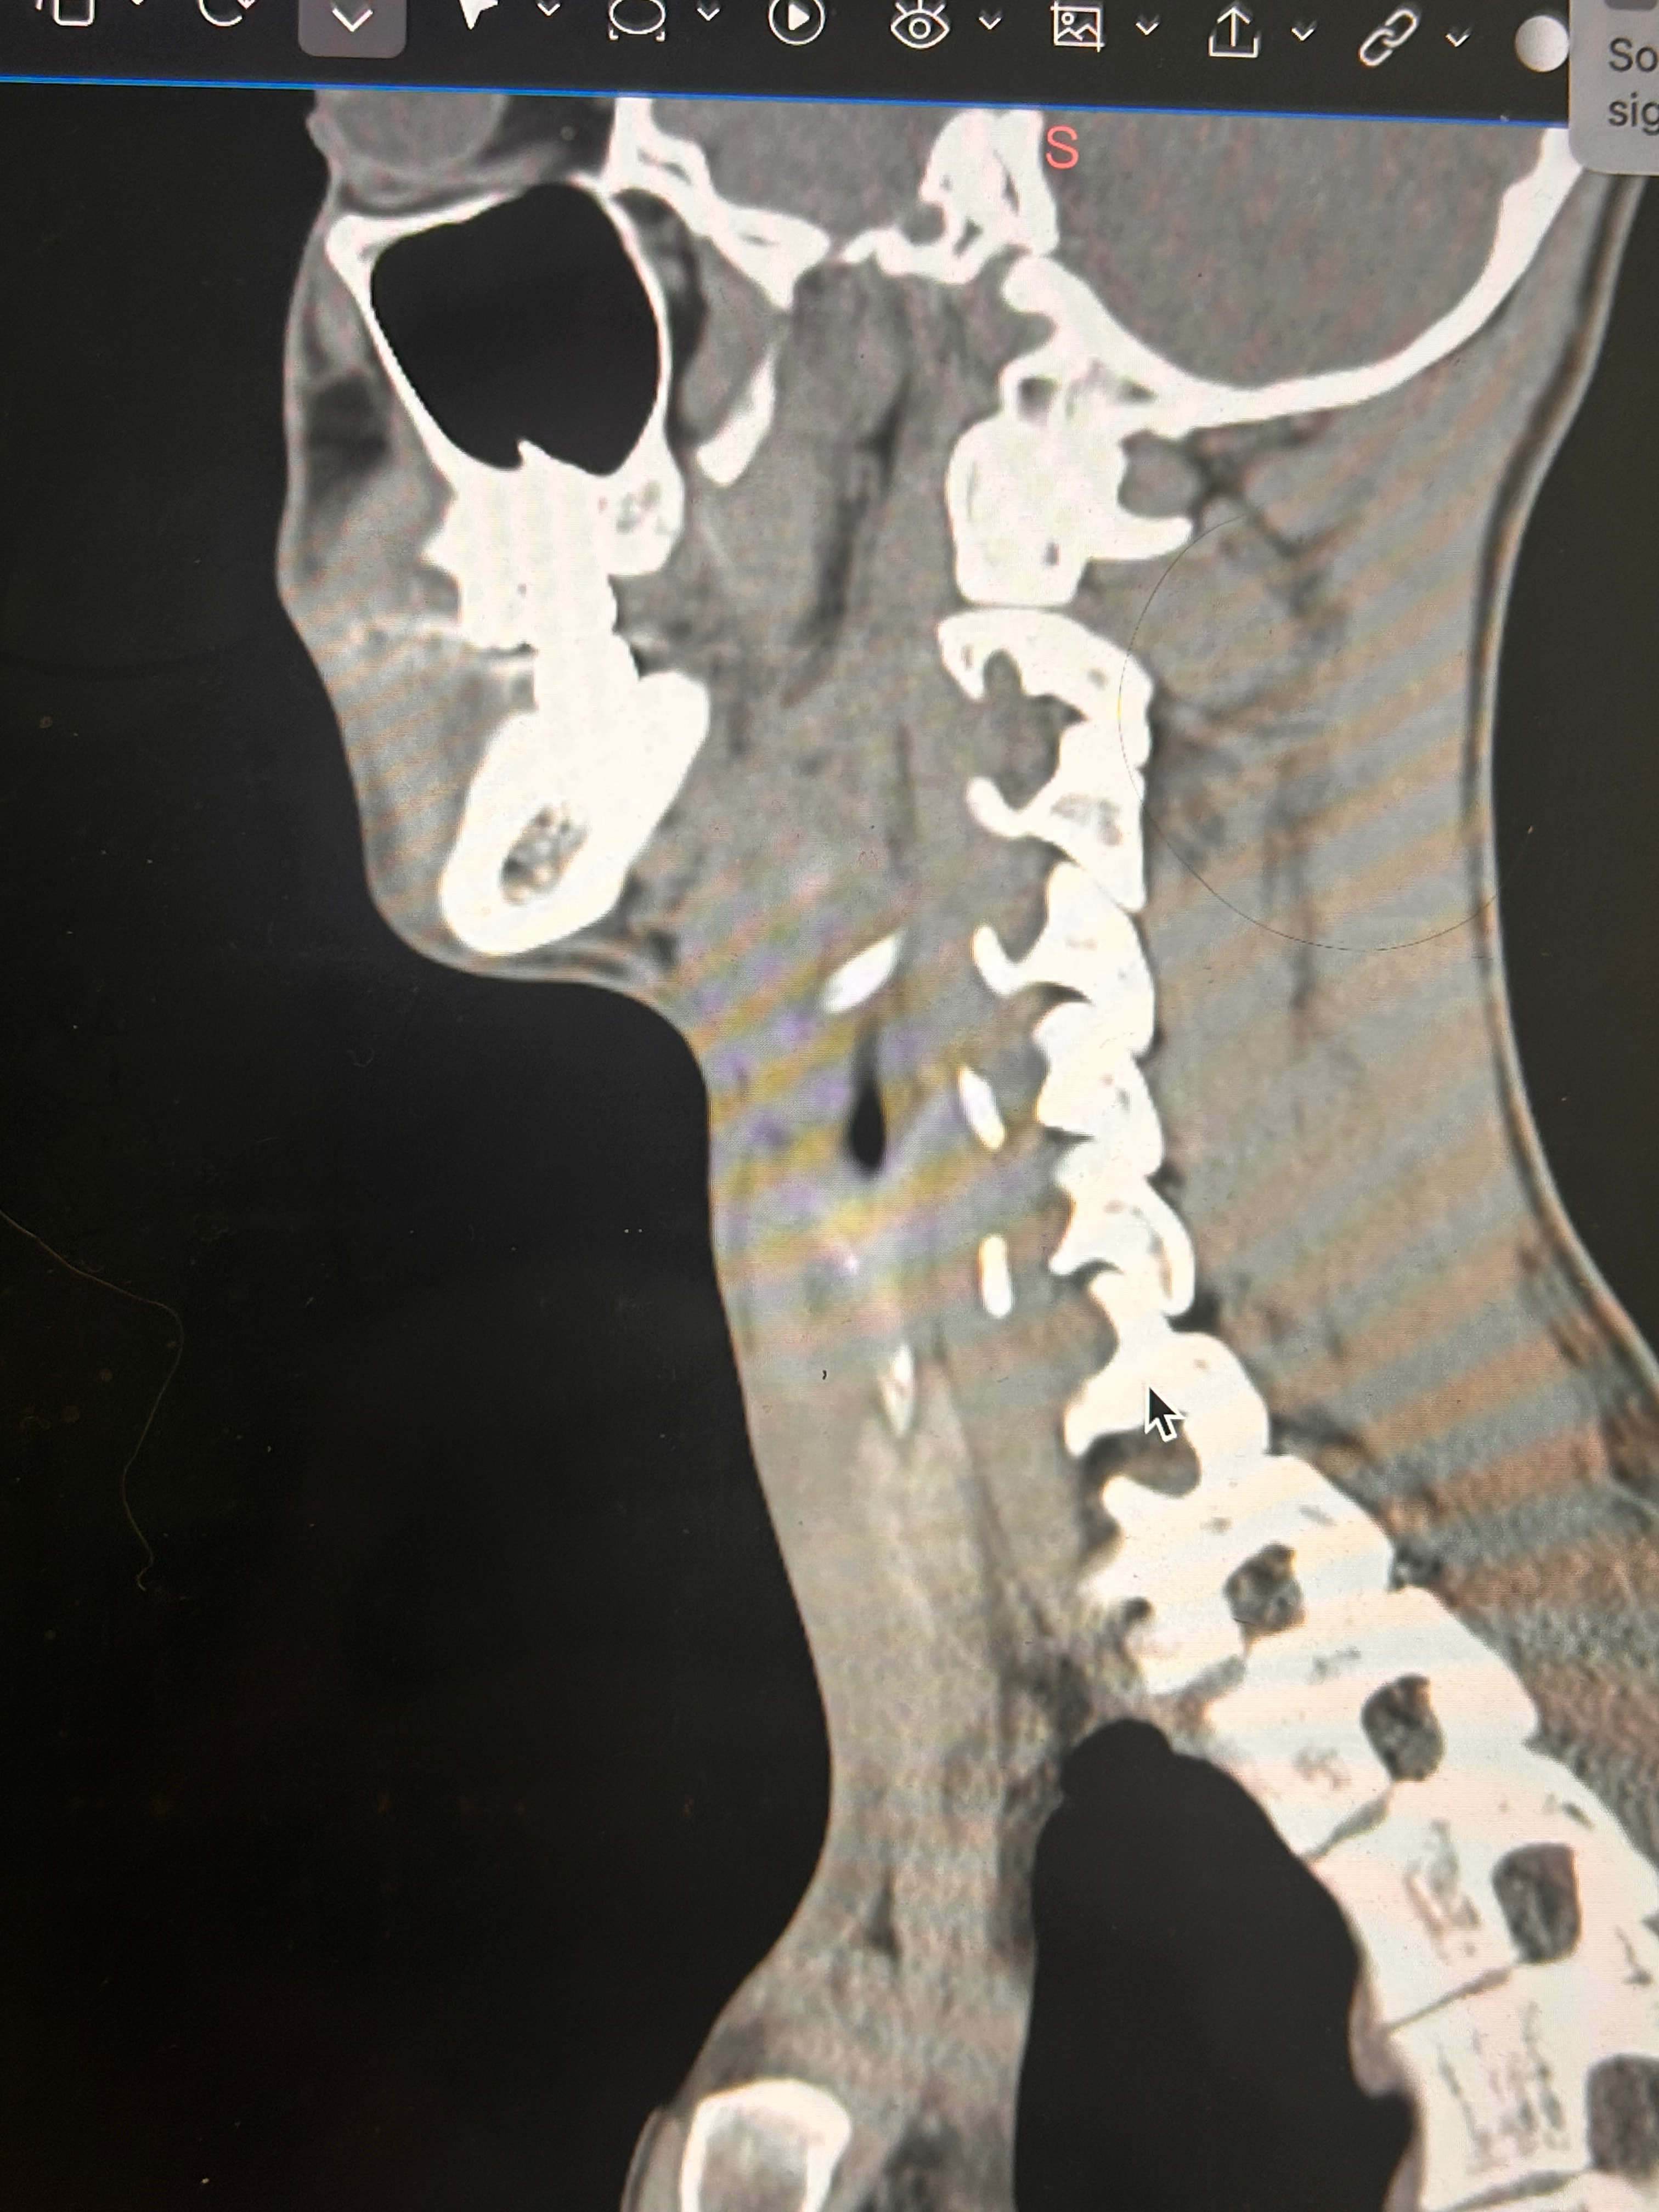

Things of note that I can see in your imaging - You’ve completely lost the natural lordotic curve in your cervical spine. That alone can bring the styloids & hyoid bone into closer proximity to nerves & vascular tissues in the neck though it has been speculated that the neck curve is lost when there’s IJV compression due to ES as the body’s way of trying to create more space for the IJV so it can drain the deoxygenated blood from the brain more efficiently. The lordotic curve can be restored w/ gentle exercises but it takes patience & is a slow process. The following link has helpful information about cervical curve restoration.

In this image of your left styloid, it appears from the angle of the picture that your left styloid is extremely close to the left transverse process of C1 (green circled area). If that’s truly the case, your left IJV is likely being squashed between the two & that means your vagus nerve is most likely being squashed at that point, too. Some of your symptoms could be vagal related. Also due to the angle of the image, it appears the greater horn of your hyoid could be very close to your spine which can cause internal/external carotid artery compression but can also cause symptoms that point to hyoid bone syndrome as you’ve suggested. Unfortunately, it doesn’t appear the CT scan was done w/ contrast as none of your veins or arteries appear in the images you posted & contrast is necessary to see those.

I’ll just add in as well that in your first image, the hyoid bone processes look pretty thick, more than you’d expect, so could well be part of your issues, but I do agree with @Isaiah_40_31 that your left styloid is very close to the C1 process, the right side looks a little longer than average… Also looking at the 1st & last images (I’m sorry, | can’t label them for you), there’s calcification below your hyoid which I’m presuming is the thyroid cartilage, it lookd pretty chunky compared to most people’s, so this could possibly be causing some issues too?

Yes these are from before my first surgery with Dr. Osborne and I had my right styloidectomy. I have also wondered about the cartilage. Last year I saw a couple of orthopedic doctors, one of whom suggested that I look into the cartilage because of how large it was and how it might be affecting my military neck and my ability to extend my neck.

Thank you so much I really appreciate you labeling things and being as detailed as you are. I think that you could definitely be onto something. I feel as though I have gotten better feedback from you and Jules than I have from my visits to Kaiser. I’m going to try to get a couple images from the Sagittal plane for you to look at. I have other symptoms that I haven’t mentioned just because there are so many like eye and tongue tension, really tense muscles from the top of my head to my shoulders. I also notice especially at night while I am lying down it seems to aggravate whatever is going on, and that is when I most notice the visual disturbances. I also contstantly feel the need to swallow, and sometimes I feel a choking sensation. Thanks again!